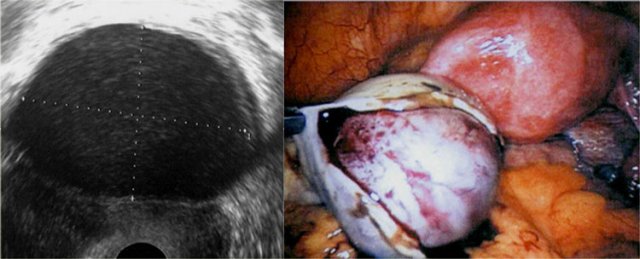

The T2- and fatsat T1-images on the left show a patient with endometriosis in whom the ovaries are stuck together ('kissing ovaries'), as a result of extensive adhesion formation.

In this patient a small hemorrhagic cyst of the left ovary and a hemorrhagic superficial plaque are also shown (high signal on T1 red arrows).

These images are of a patient with an endometrioma of the right ovary (yellow arrow).

It demonstrates intermediate signal on T2 and high signal intensity on T1-fatsat.

In addition there is:

- Hydrosalpinx with high signal on T2WI and low signal on T1-fatsat (red arrow).

- Leiomyoma with low signal intensity on T2WI and intermediate signal on T1-fatsat (blue arrow).